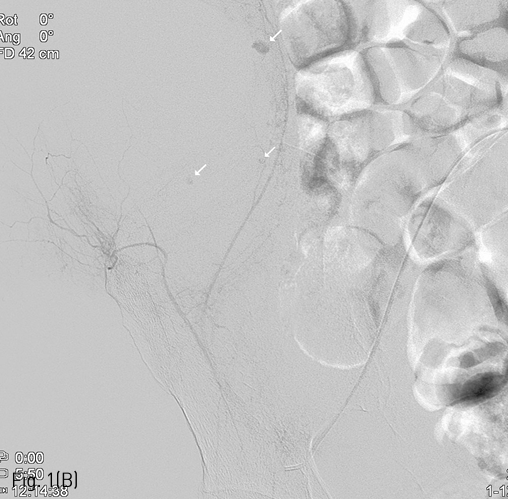

Fig 1B

(B) Multifocal extravasation of contrast media from the small branches on right deep iliac circumflex angiography (arrows), which was followed by glue embolization.